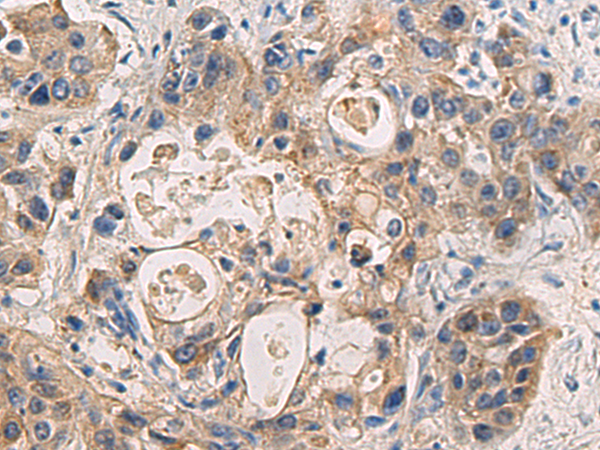

分类: 科研抗体货号: P06470别名: EVI1; MDS1; KMT8E; PRDM3; RUSAT2; MDS1-EVI1; AML1-EVI-1应用: WB,IHC反应种属: Human, Mouse